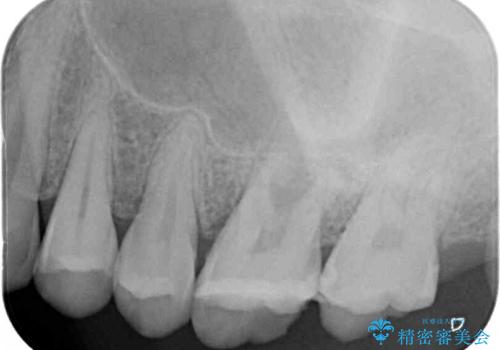

歯が割れているかどうかは、顕微鏡下で破折を確認することになりますが、割れていなかった場合には根管治療を行った上で補綴治療を行うことになるため、破折が確認できるまでは根管治療を行う前提で治療を進めて行くこととしました。

初診時の診察所見では、破折の可能性は低く、根管治療を前提とした治療にて説明をしておりました。

詰められた材料や壊死した組織を除去したところ、鮮明な破折線が認められたため、速やかに抜歯し、傷や骨の治癒を待って、サイナスリフトにより骨高さの低い部分にインプラント埋入を行いました。